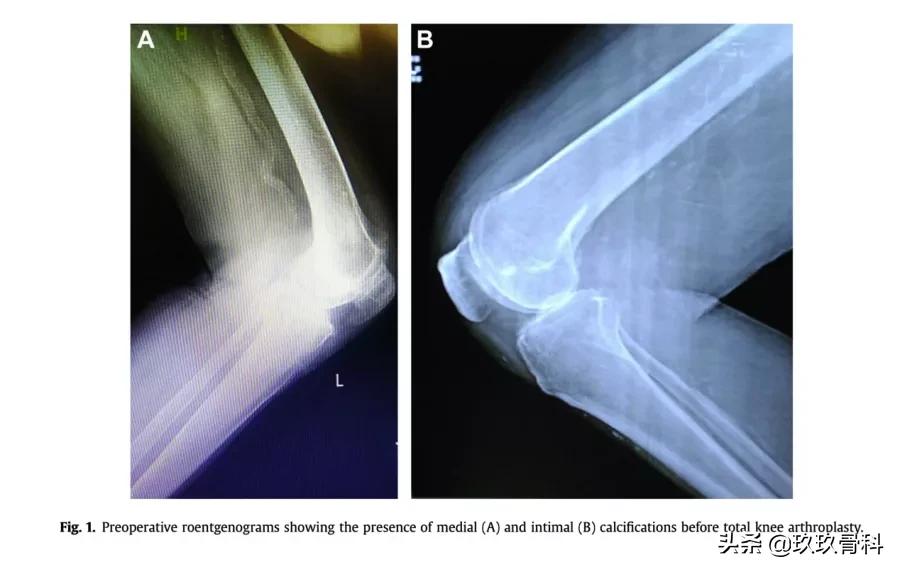

背景:在有动脉钙化放射影像患者的全膝关节置换术(TKA)期间使用止血带是有争议的。人们担心动脉内膜钙化会与缺血性并发症(例如切口延迟愈合和动脉血栓形成)相关,而中膜钙化会使动脉壁变得僵硬,可能导致止血带失败和失血增加。

方法:我们进行了一项前瞻性队列研究,包括本病区5年中2548例连续初次全膝关节置换。以确定术前大腿X线片有或无动脉钙化患者的止血带失败(充气至300 mm Hg),输血,切口愈合和缺血性并发症的发生率。其*共中**有86例显示血管钙化:中膜钙化58例,内膜钙化28例。

结果:与无血管钙化相比,有血管钙化的大腿有更高的止血带失败风险(P <.001),但输血发生率没有显着增加。钙化组的所有止血带失败病例均发生在大腿中膜钙化,而对照组的所有止血带失败病例均发生于肥胖患者。有或无动脉钙化肢体的切口愈合和缺血并发症没有差异。

结论:术前X线片上存在动脉钙化增加了TKA患者在300 mm Hg压力下发生止血带失败的风险。而输血,切口愈合或缺血性并发症的发生率没有显着增加。

图1.术前放射线显示全膝关节置换术前存在中膜(A)和内膜(B)钙化。